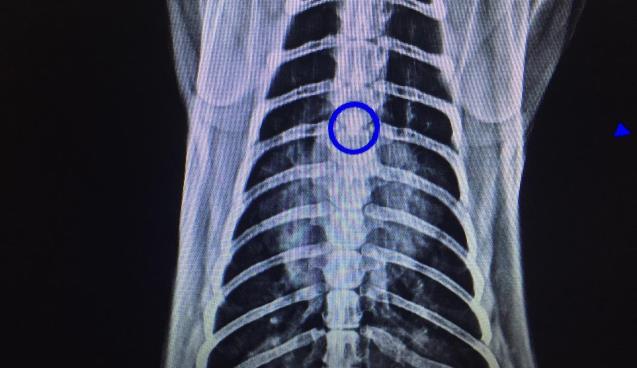

Kedinin soluk borusundan çıkan cisim şoke etti